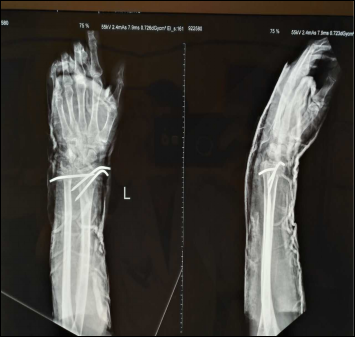

近日,一名患者因桡骨远端骨折来我院就诊,以往针对这一情况,医生会采取保守治疗,例如夹板和石膏固定,这样的治疗方法虽然可以起到一定治疗效果,但有时也会不同程度引起关节僵直、术后恢复困难等情况。为了让患者得到更好的治疗、更快恢复,我院微创骨科医生卢伟达通过进修学习的先进技术,采取桡骨远端骨折闭合手法复位克氏针内固定术,为患者的骨折部位“穿针引线”,这种方法不仅可以让骨折处的桡骨恢复得更好,而且医疗费用也相对较低。手后,患者表示感觉很好,并没有哪里感觉不适。

一般情况下,患者采取这样的治疗方法,患处没有较大的切口,骨膜损伤的可能性也大大降低,发生延迟愈合和骨不连的机率明显降低,且手术两三天就可以出院,适用人群也十分广泛。据医生介绍,治疗方法一般适用于上臂肱骨骨折、小儿前臂的骨折,还有尺桡骨前臂的骨干骨折,针对关节周围都可以用克氏针来进行固定。

另外,在我院微创骨科,前臂尺桡骨多段粉碎性骨折也有专门的治疗方法。采取闭合手法复位弹性针内固定术,结合科室之前推出的mipo微创接骨板内固定术,对于单、双段骨折,利用针、板结合的方式,为患者进行准确定位治疗。从临床效果来看,一般患者在进行手术后的10天,疼痛和肿胀的情况明显减轻,大大避免了麻痹、创伤等危险,让骨折愈合速度加快,优势明显。